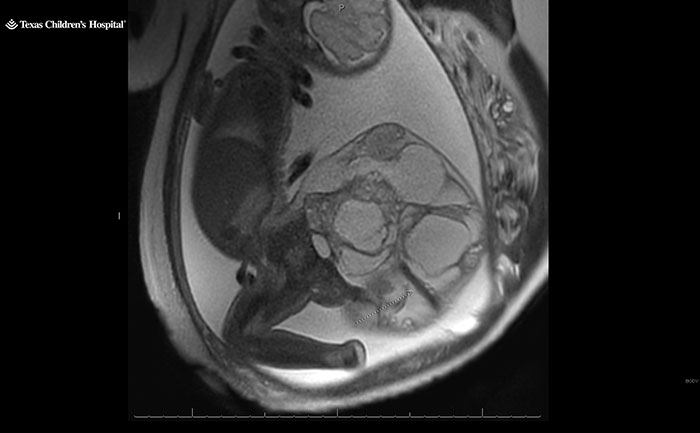

At Kristin Tyler’s 20-week anatomy scan in February 2024, she and her husband Jacob Tyler were told that their baby might have spina bifida, a birth defect that can damage the spinal cord and nerves. “I didn’t even know what that was,” Kristin told People on Monday (October 7). “So I was freaking out.” A specialist subsequently diagnosed their unborn daughter with a sacrococcygeal teratoma instead, a rare fetal tumor that forms from the baby’s tailbone.

Share icon Image credits: Kristin Tyler As a result, the couple, from Alexandria, Louisiana, USA, was referred to the Texas Children’s Pavilion for Women in Houston to be monitored by a specialized care team. They traveled 245 miles (approximately 394 kilometers) from home to meet Dr. Ahmed Nassr, a maternal-fetal medicine specialist and fetal surgeon at Texas Children’s Pavilion for Women, People reported. Dr. Nassr explained that the tumor was “very rare” and that it occurs in girls more often than boys, in addition to being usually benign. A benign tumor isn’t a malignant (cancerous) tumor. It grows more slowly than a cancerous tumor, has even borders and, unlike cancerous tumors, it won’t spread to other parts of your body, the Cleveland Clinic explains. Share icon Image credits: Texas Children’s Hospital In most cases, doctors don’t know why it happens, as Dr. Nassr told People: “It’s just bad luck.” Moreover, the tumors can grow very large. As they grow, the tumors can develop large blood vessels. “They basically steal the blood supply from the baby,” Dr. Nassr explained. “The heart of the baby needs to work very hard,” which, he said, can lead to heart failure. In March, Kristin temporarily relocated to Houston, Texas with her one-year-old son William and her mother, so doctors could continue to monitor the baby. Meanwhile, Jacob, a mechanic, reportedly had to stay in Louisiana and work.

Born at 34 weeks, Adalida Tyler survived a 16-centimeter sacrococcygeal teratoma tumor

Share icon Image credits: Texas Children’s Hospital “I was very scared,” the 23-year-old mother-of-two told People. “After so many doctor appointments and seeing it on the ultrasound, it was scary.” Kristin had kept the situation shielded from friends and family, as she recalled: “There was nobody for me to reach out to talk about it. It felt like we were in the dark.” On May 21, at 34 weeks, Kristin delivered Adalida via C-section. The little baby girl was born with the dreaded four-pound tumor, nearly two-thirds of her body weight. Combined, the baby and tumor weighed more than 10 pounds (approximately 4.5 kilograms). Dr. Nassr recalled the tumor size being “a little bit smaller than a watermelon,” but larger than a cantaloupe. Share icon Image credits: Texas Children’s Hospital He told People: “It was a big tumor, that’s why we were so worried. “We needed to be very careful during delivery. “We had to avoid any trauma or rupture of the tumor. Because sometimes with that large of a tumor, it can rupture and can start bleeding, and baby can become very sick after delivery.” Kristin, who had only been able to see Adalida for a “split second” through a TV camera, recalled the moment her daughter was immediately taken to the neonatal intensive care unit: “I had just had her, and I was crying and I was upset.”